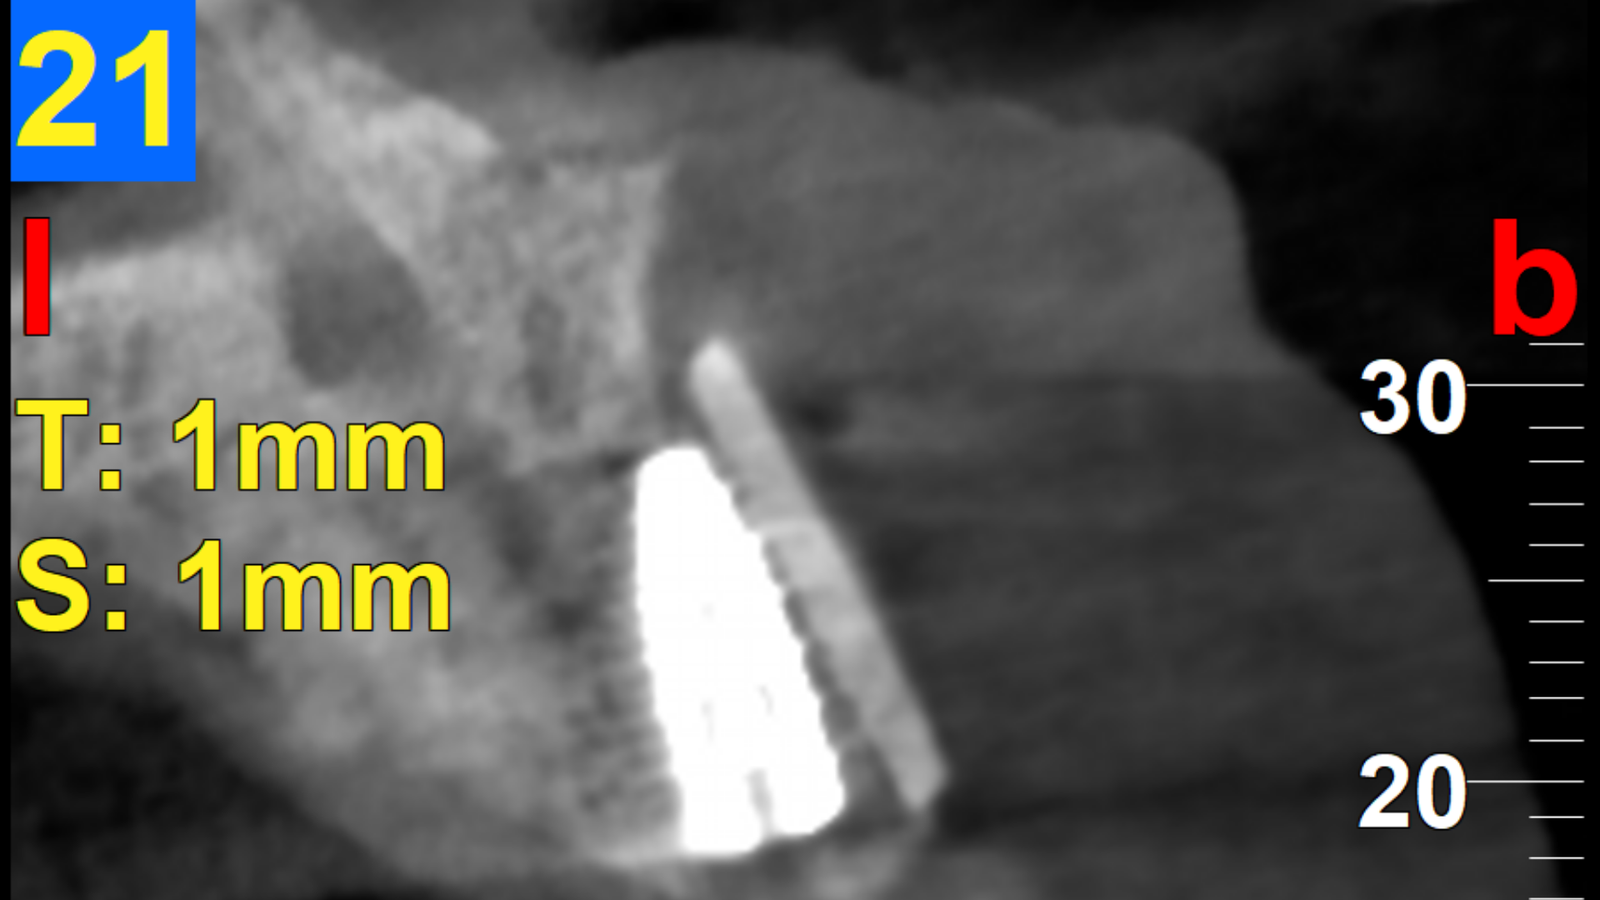

Un patient se présente avec une incisive centrale droite (11) dévitalisée, ainsi que l’incisive latérale homolatérale (12), également dévitalisée.

Ces deux dents présentent des images de résorption osseuse discrète en rapport avec la dévitalisation, avec un kyste de 12 mm au niveau de la 12.

11 : extraction avec greffe osseuse (mélange os bovin + os du patient prélevé au niveau du ramus), le tout recouvert d’une membrane et fixé avec des pins.

12 : résection de la partie apicale avec un remplissage rétrograde au MTA.

À 6 mois : mise en place d’un implant.

3 mois après : mise en place d’une couronne vissée en zircone.